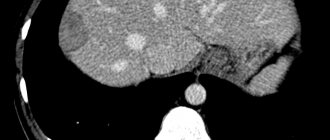

Полигепатография вовремя выявляет нарушения печени и даёт возможность оценить состояние обмена веществ в органе. Этот метод позволяет сопоставить результаты других исследований:

• ультразвуковое;

• компьютерное;

• магниторезонансной томографии;

• анализа крови на альфа-фетопротеин.